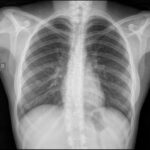

Entre las aplicaciones más habituales destaca la radiografía de tórax. Este estudio permite evaluar el parénquima pulmonar, el tamaño y la silueta cardíaca, la presencia de derrames pleurales y múltiples patologías respiratorias agudas o crónicas. Su utilidad se debe a la marcada diferencia de densidad entre el aire pulmonar y las estructuras sólidas, lo que genera un contraste natural elevado.